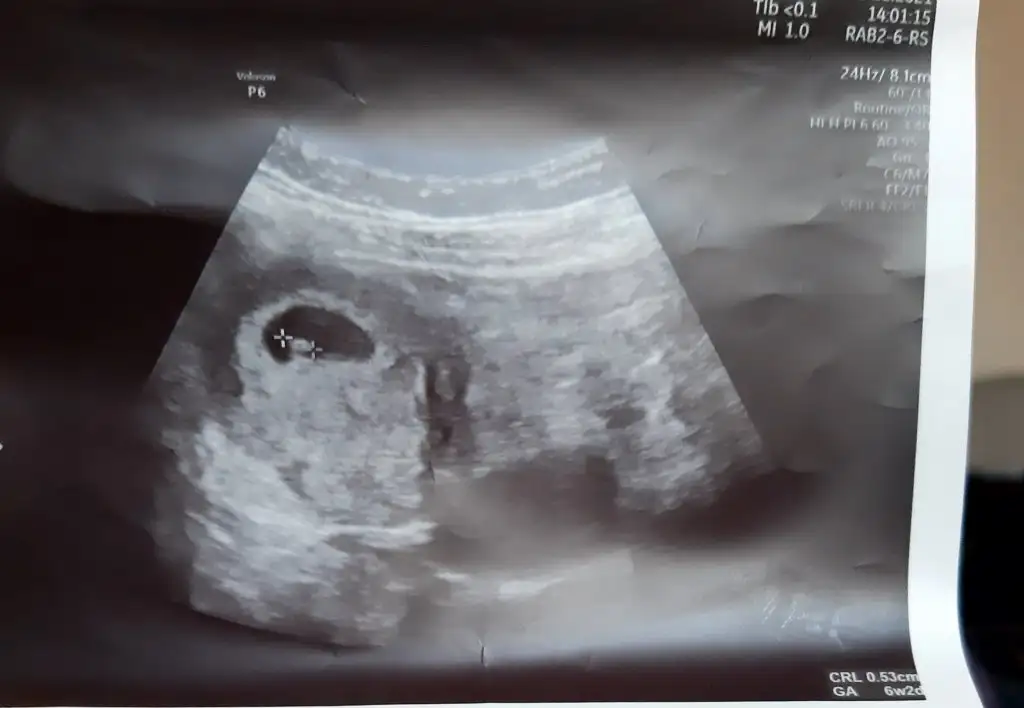

12 Kasım 2513.42 çıktı. Doktor ağrılar normal ama daha önce düşüğün olduğu için riske girmeyelim dedi iğne verdi. Vajinal ultrasonda keseyide gördükBenim miniğime bi bakın bakalım. Bir de beta hcg sanki biraz yüksek gibi sat 10 ekim onu da anlamadım.